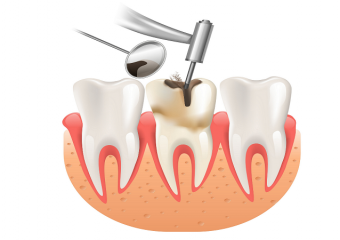

روت کانال دندان چه عوارض و خطراتی در پی دارد ؟

خطرات احتمالی و عوارض عصب کشی دندان

پروسه روت کانال دندان برای نجات دندان شما انجام میشود. با این حال، گاهی اوقات، آسیب وارد شده به مغز دندان بیش از حد عمیق است یا مینای دندان شما برای تحمل عصب کشی بسیار ضعیف است. این عوامل می تواند منجر به از بین رفتن دندان شود. در نتیجه در اغلب اوقات دندان عصب کشی شده معمولا کشیده میشود.

چه موقع به انجام روت کانال دندان نیاز پیدا خواهیم کرد؟

عصب کشی هنگامی انجام میشود که قسمت داخلی یک دندان که به آن پالپ نیز گفته میشود آسیب ببیند و یا دچار التهاب و عفونت شود. حتی اگر پالپ یا مغز دندان از بین رفته باشد و یا در اصطلاح مرده باشد، بخش بالایی دندان یا همان تاج () میتواند کماکان دست نخورده باقی بماند. از بین بردن پالپ دندان آسیب دیده یا آلوده، بهترین روش برای حفظ ساختار دندانها است.

علل عمده صدمه به پالپ شامل موارد زیر است:

- پوسیدگی عمیق به دلیل عدم رسیدی و درمان سوراخ ها و حفرات دندان